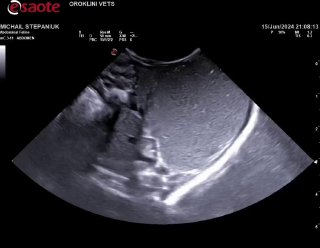

Нарушена перистальтика скорее всего, дело не в Кале, молоко не переходит из желудка дальше, а выходит обратно… надо узи. В ороклини пообещали принять, но уже 6:30, с 2 жду((( никто не пришел туда